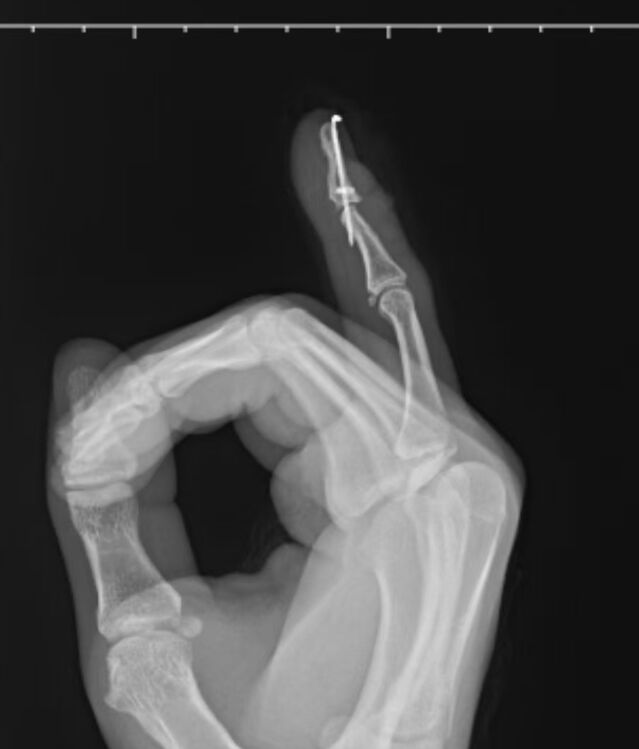

克氏针斜行固定DIP关节与垂直贯穿固定有3个优点:

1,进针点比末节指骨尖端宽大,容易进针。

2,不会误穿到甲床下,损伤甲基质,引起甲板畸形或者甲根坏死。

3,克氏针针尾留在指侧方,比留在指端安全,减少不慎勾住衣物拔出的风险。

术中白主任也同意我的观点,他还提出另外一个优点,就是

4,一旦出现断针,针尖部分也可以从侧方取出来,因为大多数情况是克氏针穿透中节指骨两层皮质,从指侧方出来的。

微信截图_20250826174438.png

微信图片_20250826174508.png